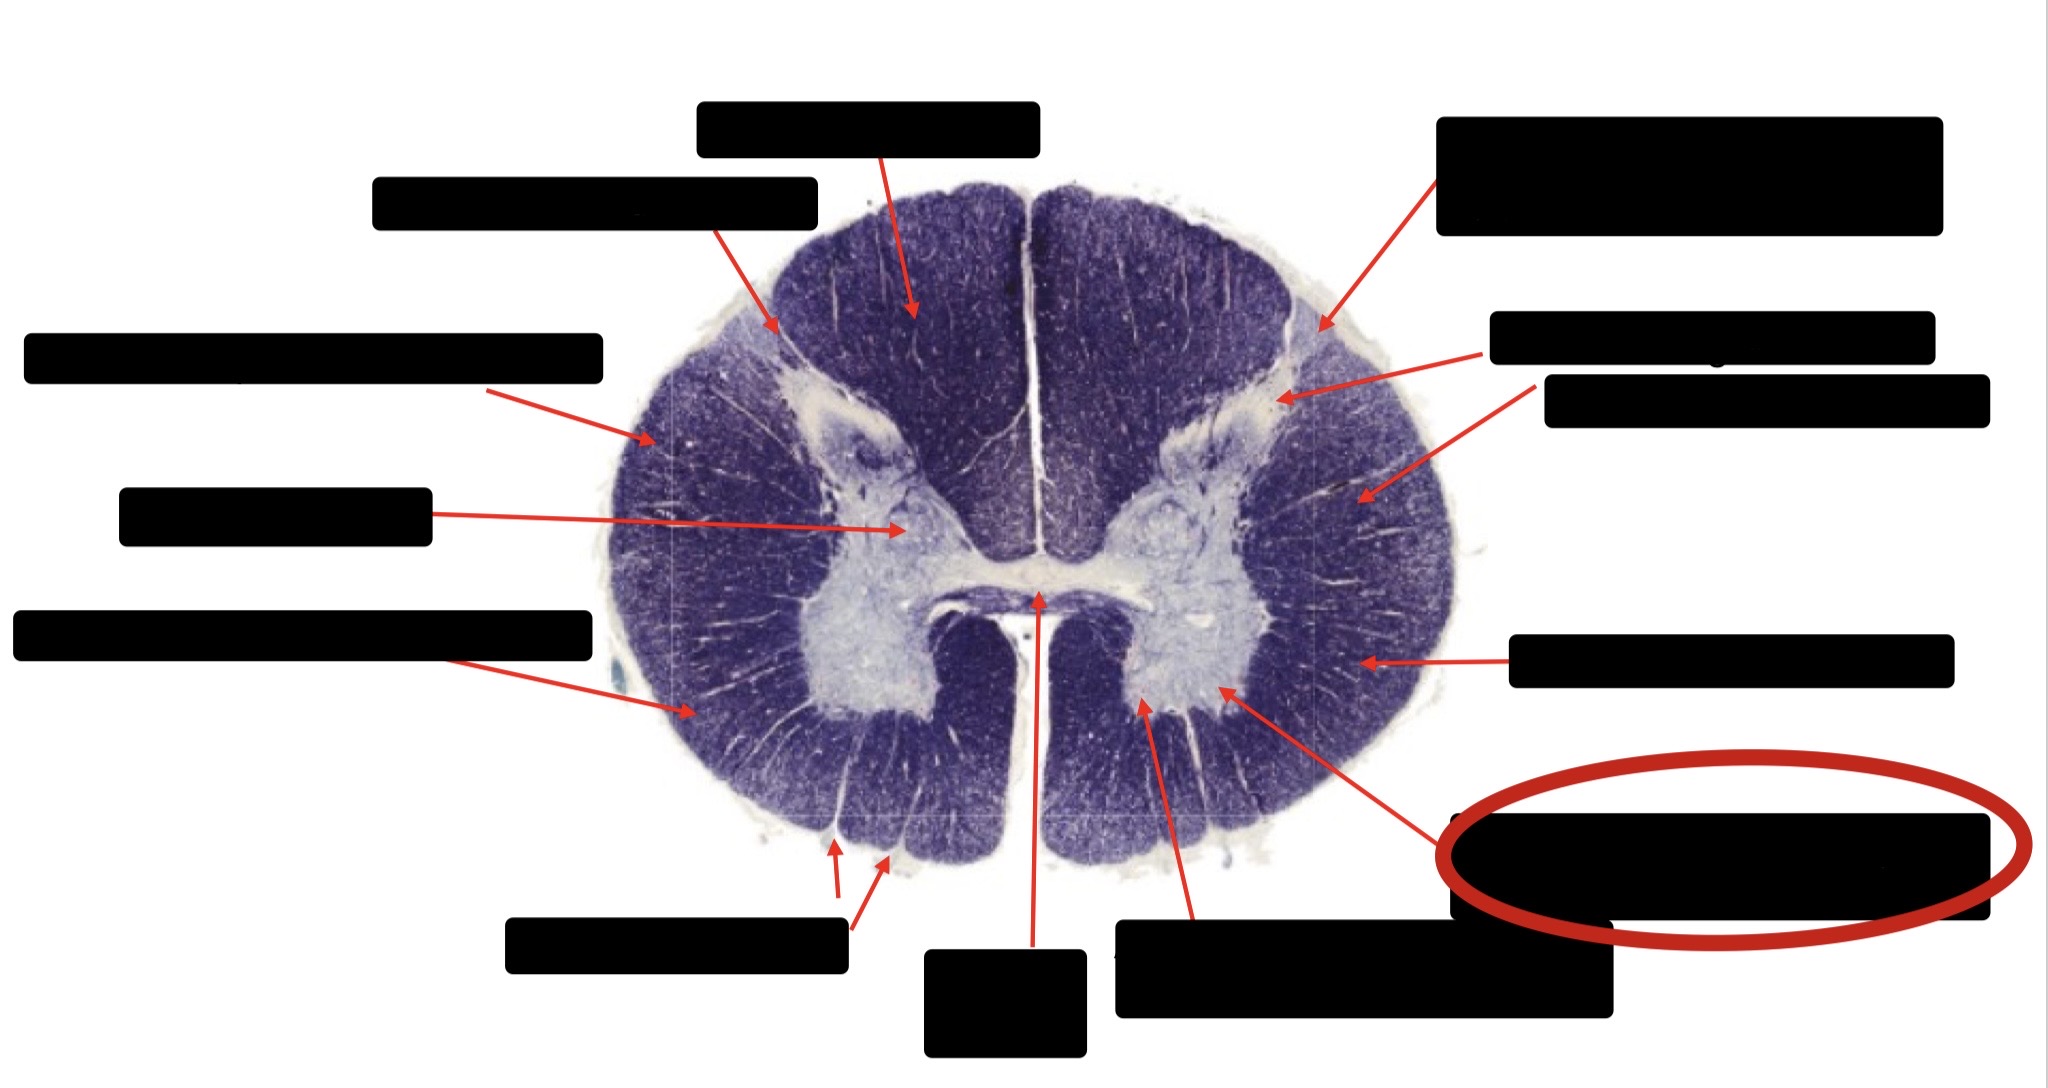

Central Canal

Posterior Column (Fasciculus Gracilis)

Large Fiber Entry Zone

Lissaeur’s Tract & Small Fiber Entry Zone

Substantia Gelatinosa

Lateral Corticospinal Tract

Ventral Root Fibers

Anterior Horn Motor Neurons

Anterior Medial Fissure

Dorsal Rootlet

Posterior Spinocerebellar Tract

Anterior Spinocerebellar Tract

Spinothalmic Tract

Posterior Column (Fasciculus Cuneatus)

Anterior Horn Motor Neurons (Distal Muscles)

Anterior Horn Motor Neurons (Proximal Muscles)

Anterior Corticospinal Tract